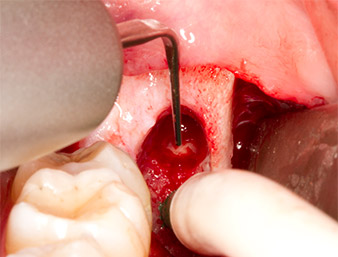

Tras una anestesia local y por conducción, el campo quirúrgico se abrió mediante los tejidos blandos para tener un acceso bucal-retromolar y se dejó expuesto (figura 3).

El tejido situado por encima del resto radicular no se había osificado por completo y constaba en su mayor parte de un tejido granulado con alteraciones inflamatorias (figura 4).